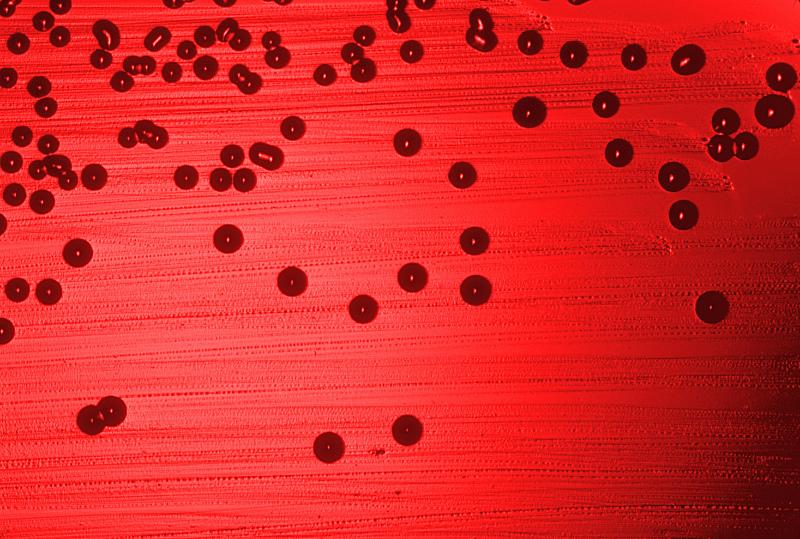

Стафилококковая инфекция: ваш полный гид по лечению и профилактике

Столкнулись с трудноизлечимой инфекцией или подозреваете у себя стафилококк? Эта статья представляет собой исчерпывающее руководство по стафилококковой инфекции, её видам, симптомам, современным методам…